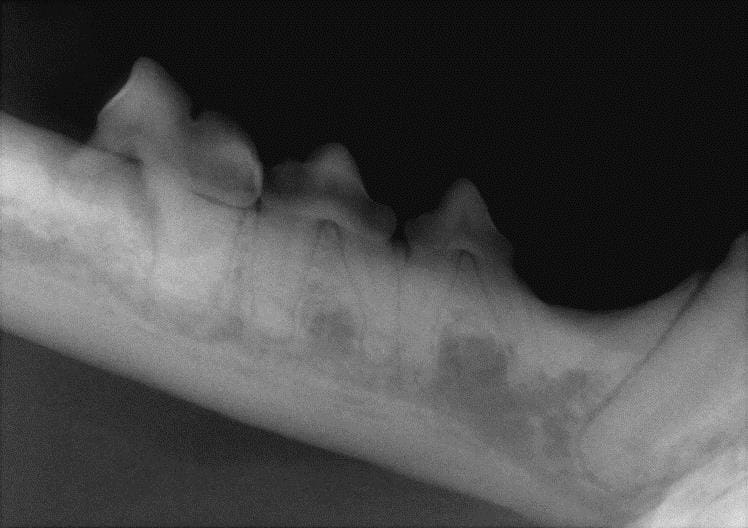

Normal Canine Dental Radiographs Vet Dent Edu Veterinary Dental X Ray Cpd Learn what’s normal and what normal. Our wide range of veterinary dentistry courses cover everything from preventative care, dental clinics, and. Oral radiography techniques are shown in. Cpd online webinars allow you to further your veterinary career via distance learning. This learning series, with rachel perry, is suitable for both vets and vet nurses and covers all aspects of dental. Veterinary Dental X Ray Cpd.